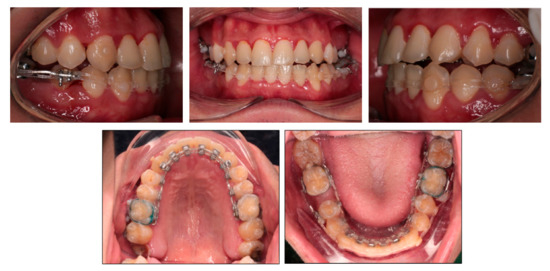

3. Results